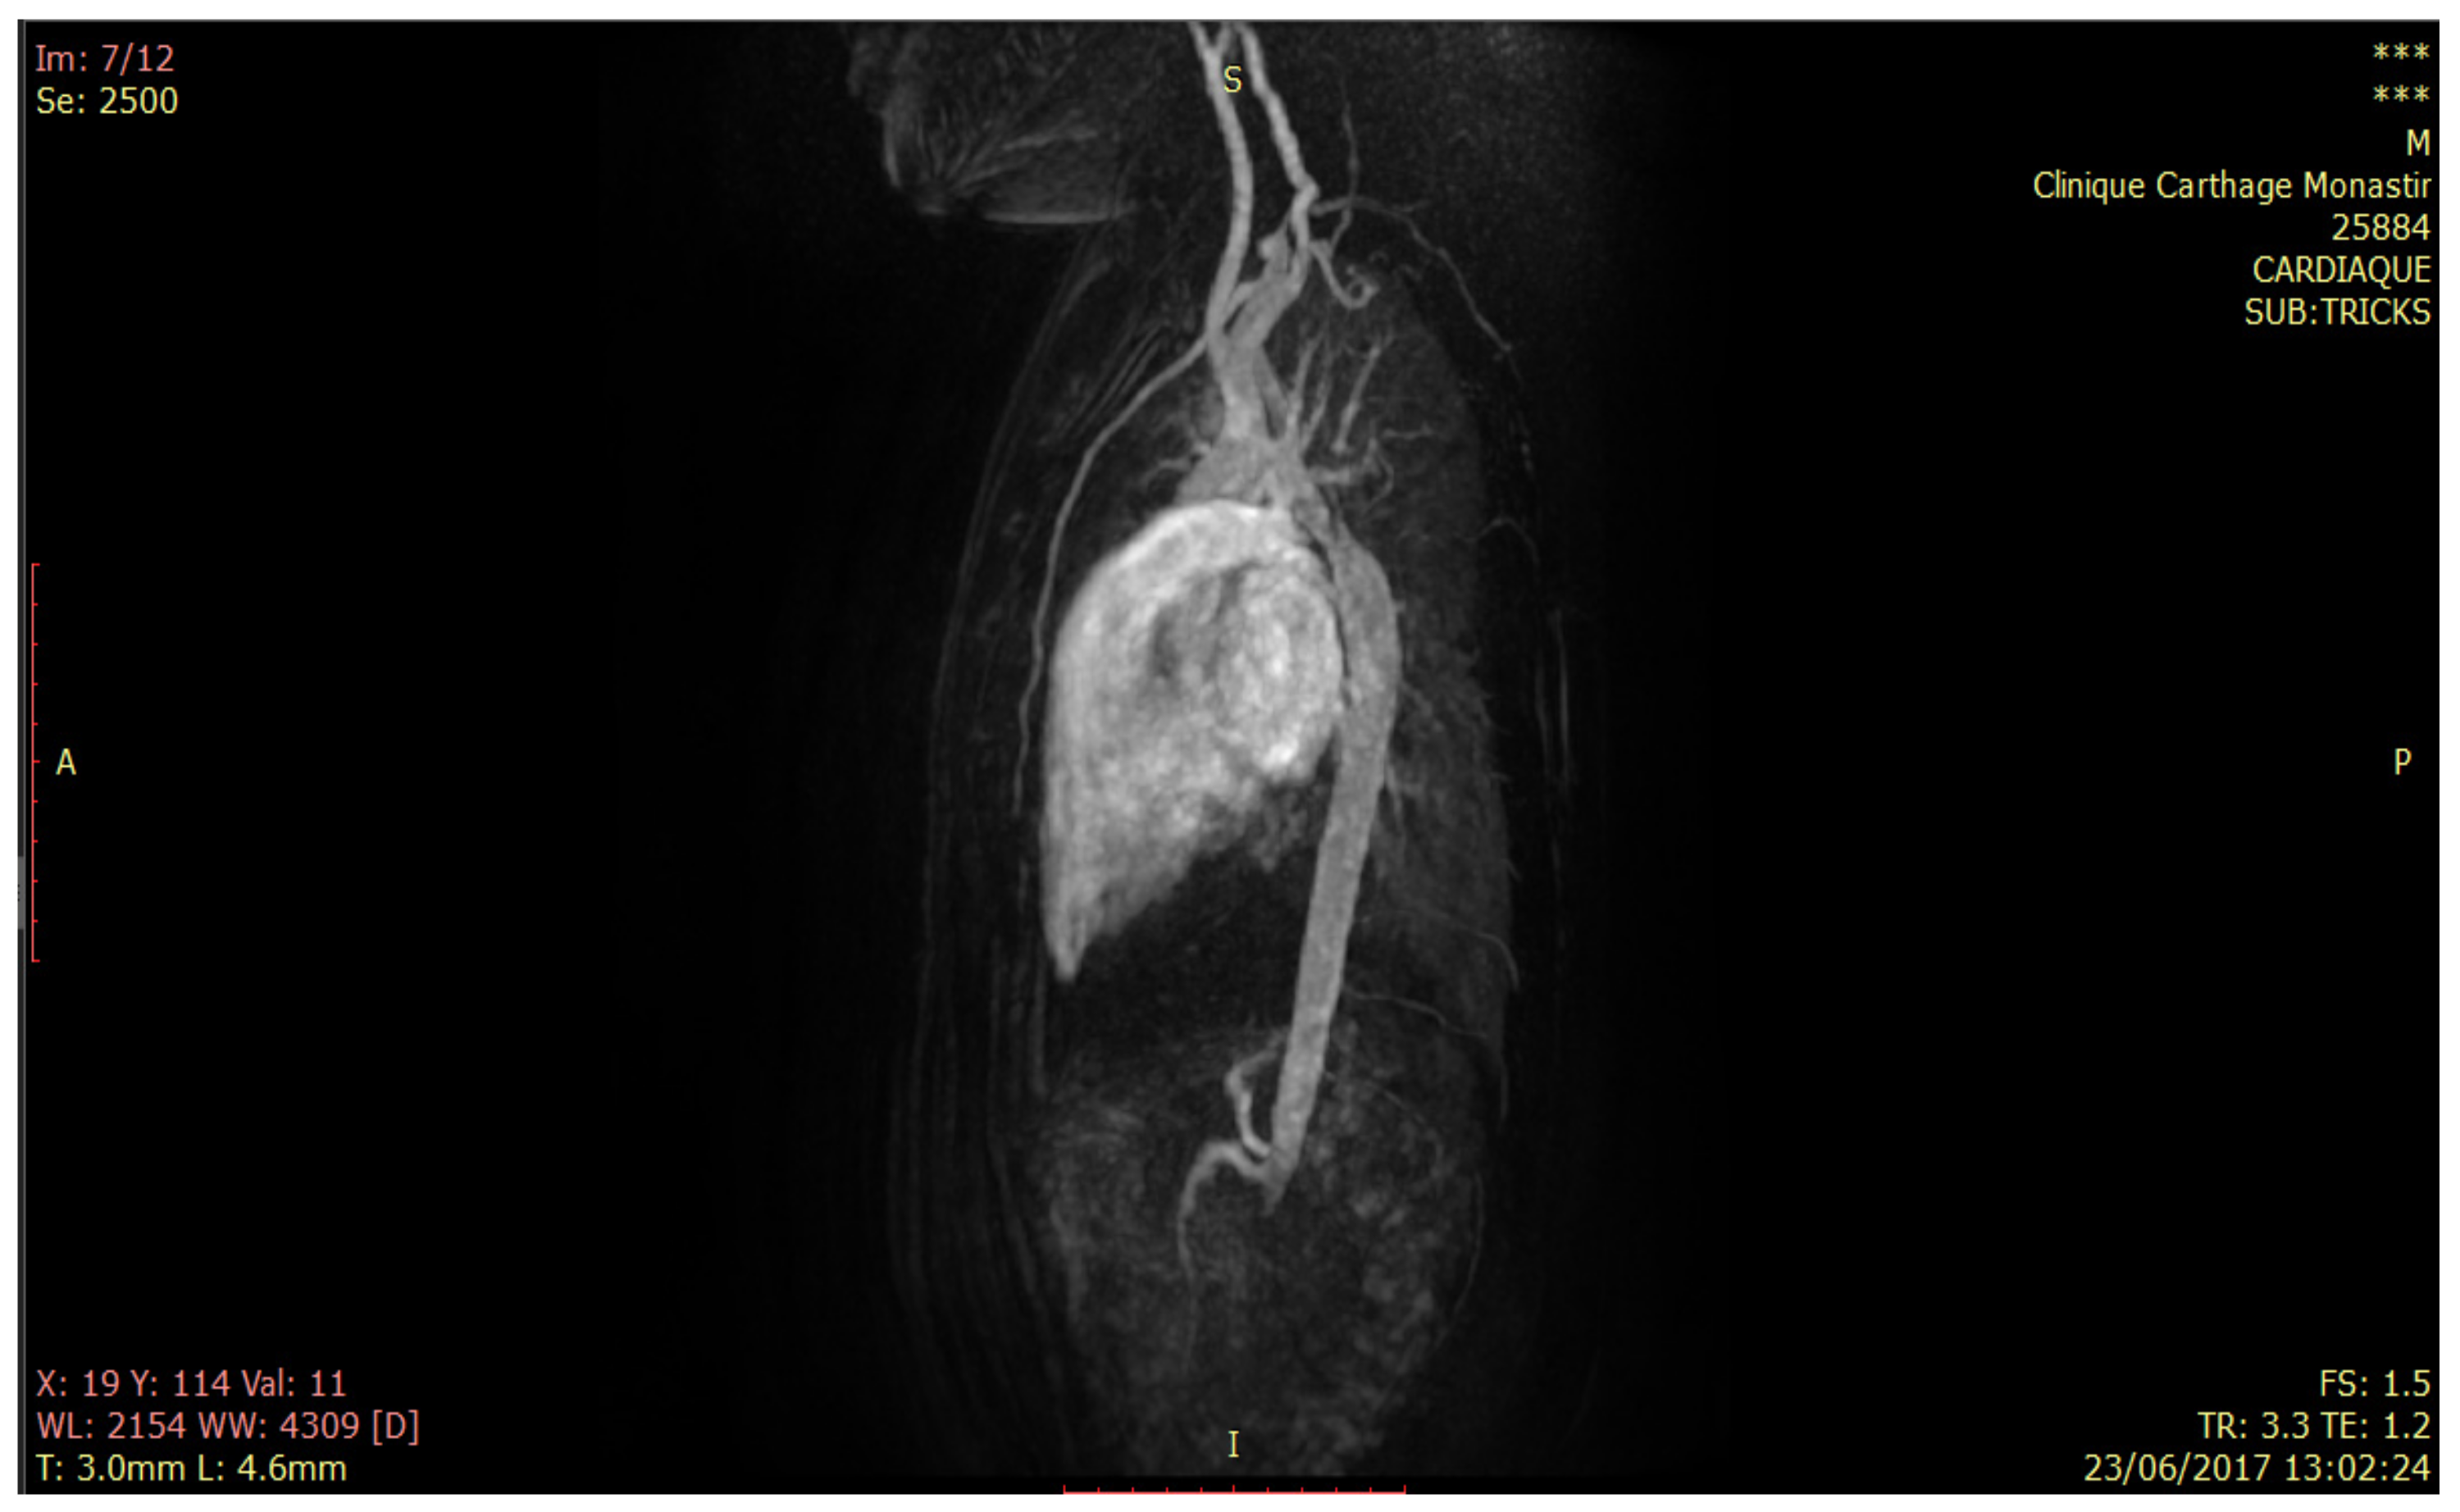

- 44 TRICKS angiographic slices in dynamic acquisition on the thoracic aorta;

- Tricuspid valve. Aortic ring with 8.5 mm diameter;

- Aortic stenosis at 0.42 cm2 with reduction of sigmoid opening at 5 mm;

- At the sino-tubular junction: 25 mm;

- 1/3 medium of the ascending aorta: 18 mm;

- Horizontal aorta: 16 mm;

- Size disparity with aortic stenosis at the isthmic level extended over 10 mm, reducing approximately 65% of its lumen by 6 mm in diameter;

- Magnetic field: 1.5 Tesla;

- Acquisition time: 1.2 s/Repetition time: 3.3 s;